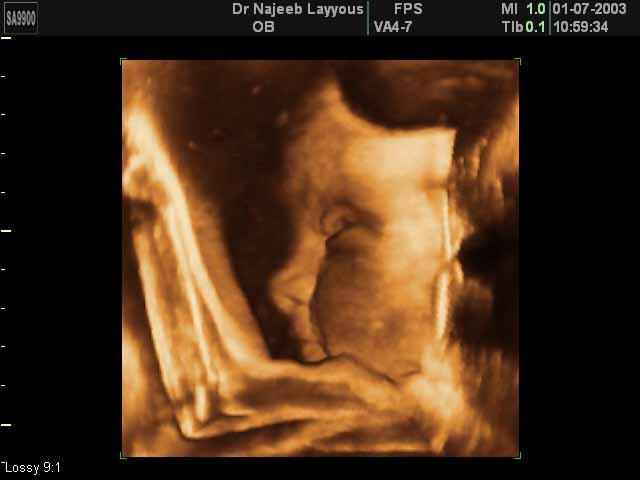

- 3D Fetal Profile Ultrasound Scan Photos